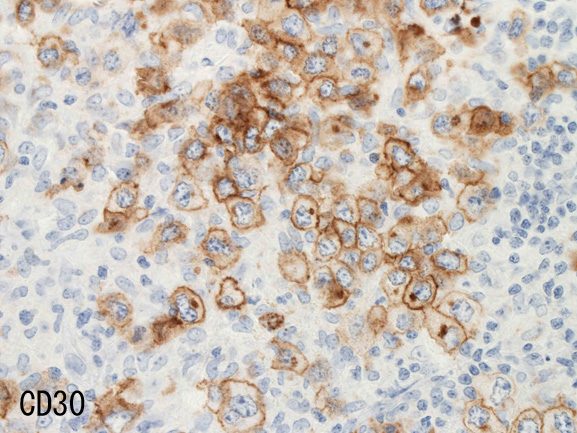

腫瘍細胞はCD20+, CD30+, CD15-, PAX-5+, Oct.2+, BOB.1+(Oct2, BOB1は田丸先生の染色結果), EBER-ISH+, EBNA2-

| CD20 | PAX-5 | CD30 | EBER-ISH+ |

- CD30は50%に陽性。CD15は陰性。